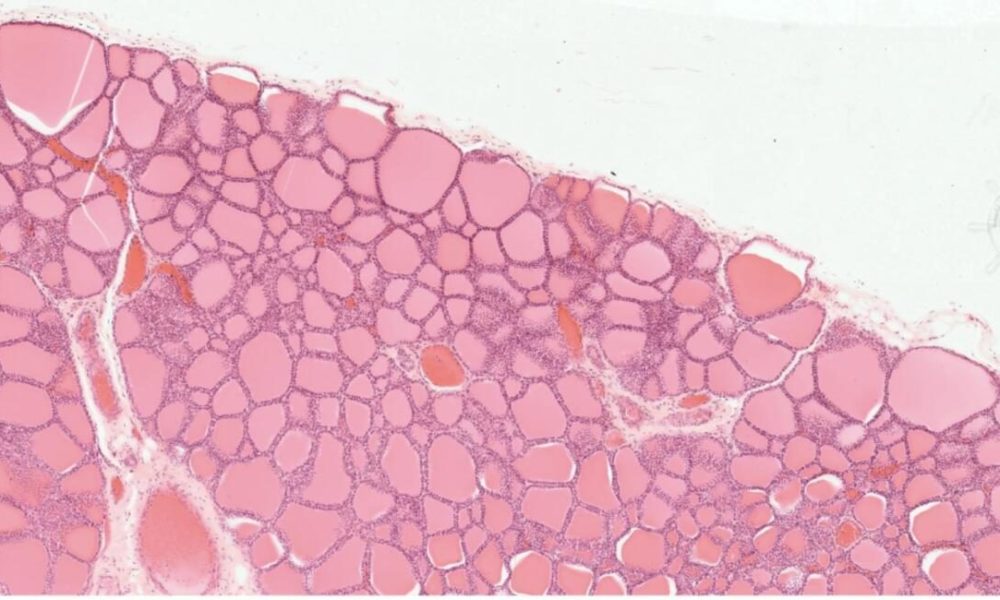

4. На фотографии представлен срез органа X. Известно, что это периферический орган эндокринной системы, имеющий паренхиматозное строение. Структурно-функциональной единицей органа X является:

ацинус

долька

сегмент

фолликул

Правильный ответ: фолликул